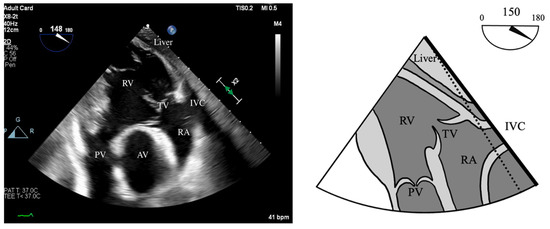

- S’: Measured from a non-standard TEE view. In the Deep Transgastric long axis (DTG-LAX) view, omniplane to 120–150° and turn right. The RV and lateral tricuspid annulus will be centered on the screen. Tissue Doppler Imaging (TDI) is then used to measure the systolic velocity of the lateral tricuspid valve annulus (S’) with >10 cm/s considered normal [79] (Figure 4 and Figure 5).